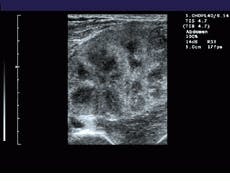

For every new image acquired, its translational and rotational displacements from the previously acquired images are determined. The next acquired image is assumed to have similar features to the previous images, but translated and rotated. Each block in the previous images is compared with the new image. An algorithm, dubbed the XFOV, determines where in the new image each block in the previous image matches best, according to a selected matching criterion, and calculates a relative motion of each block from the previous image to its best matching point in the new image (see Fig. 2). This motion occurs during the time between acquiring the previous image and the new image. The translations computed for each block in the previous images are called motion vectors.

FIGURE 2. To register images, a computational estimate of local motion between successive images is performed. Fuzzy logic simplifies the analysis of the motion of sucessive images using prior-motion history data. This makes the final motion estimation very stable, even when high amounts of image noise are present.